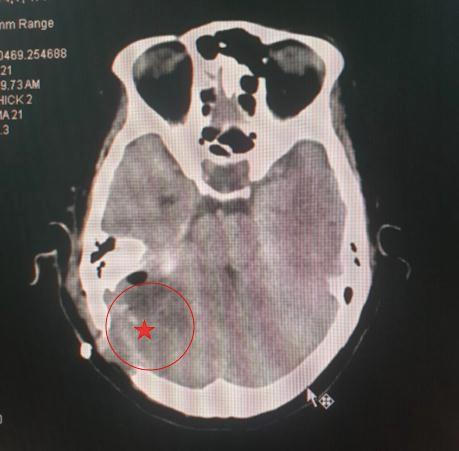

![]() |

Khối u đã được loại bỏ hoàn toàn sau phẫu thuật |